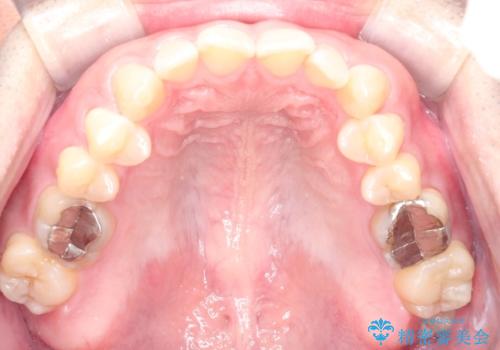

- 前歯の咬み合わせが気になるとのことで来院されました。

前歯が噛んでいない状態(開咬)のため、インビザライン矯正で改善することとしました。

前歯が嚙んでない場合(開咬)、顎間ゴムというゴムを使用してもらうことがあります。顎間ゴムは、前歯を噛み合わせるための力を与える補助的な役割があります。